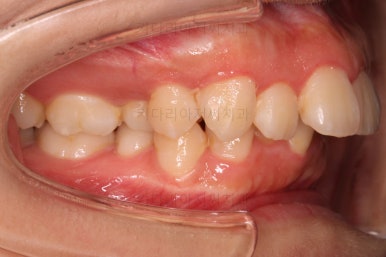

부산무턱교정치과 초진 시 입안의 모습입니다.

전반적으로 치열이 삐뚤고요. 아랫니가 윗니보다 뒤쪽으로 많이 가려져 있죠.

그래서 앞에서 봤을 때 아래 앞니가 거의 보이지 않는 상태인데요.

이런 교합을 "과개교합"이라고 표현합니다.

전반적인 교합, 치열, 과개교합, 튀어나와 보이는 앞니 등을 개선해줘야겠네요.

웃거나 말할 때 튀어나온 앞니가 강조되어 보여 입은 더 나와 보입니다.

아래턱이 작아서 옆모습에서 무턱 느낌이 들고요.

상대적으로 입은 나온 돌출입 양상입니다.